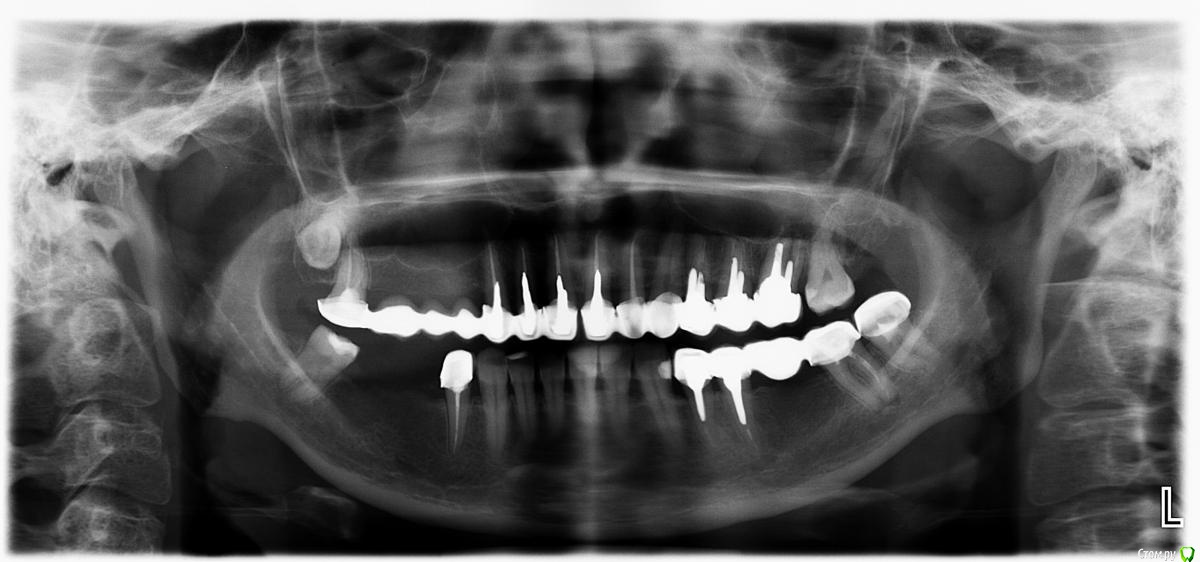

sabik Опубликовано 21 мая, 2019 Поделиться Опубликовано 21 мая, 2019 Здравствуйте, болит зуб снизу 7-ка справа (на снимке слева), болит уже второй год, причину боли не понимает никто, видимых изменений на корнях нет особых, в данный момент удалены нервы, каналов два, залили каласепт уже почти месяц как, а боль не утихает, она не острая, а тупая, ноющая, если сбоку надавить на зуб то чуть усиливается. Третий канал искали на КТ, его нет там, всего два канала, кист нет, небольшое расширение периодонтальной щели и все. Что может давать боль эту, к неврологу стоит идти? Не знаю уже что делать, ждать когда пройдет, сказали, но она не утихает, каласепт должен помочь уже или нет? Подскажите, может в вашей практике были случаи такие? Удалять не хочется этот зуб без видимой причины, может ли быть это не связано с зубом, а с невритом нерва нижнечелюстного какого-нибудь? Есть ли смысл лазером прогревать? Очень жду ваших мнений. Ссылка на комментарий

DmitrySH Опубликовано 29 сентября, 2019 Поделиться Опубликовано 29 сентября, 2019 У вас есть альтернативный вариант. Отсутствуют 2 зуба внизу справа, надо ставить 2 импланта. И можно убрать проблемный зуб и поставить тоже 2 импланта с мостовидным протезом Ссылка на комментарий

dentikl Опубликовано 29 сентября, 2019 Поделиться Опубликовано 29 сентября, 2019 Здравствуйте, болит зуб снизу 7-ка справа (на снимке слева), болит уже второй год, мостик сверху года 3 как надели? Ссылка на комментарий

sabik Опубликовано 29 сентября, 2019 Автор Поделиться Опубликовано 29 сентября, 2019 мостик сверху года 3 как надели?Мостику сверху 13 лет, и уже начал болтаться Ссылка на комментарий

sabik Опубликовано 29 сентября, 2019 Автор Поделиться Опубликовано 29 сентября, 2019 У вас есть альтернативный вариант. Отсутствуют 2 зуба внизу справа, надо ставить 2 импланта. И можно убрать проблемный зуб и поставить тоже 2 импланта с мостовидным протезом Это было б идеальным вариантом, но проблема в том, что очень тонкая кость, ее не хватает никак, боятся сломать ее, как перепонка гнется даже, ходила ко многим, но рисковать, учитывая сколько стоить еще все это будет с наращиванием кости, мало кто берется, и если берется, то гарантий не дают, поэтому и не хотелось еще и этот зуб потерять, кто-то считает, что это может быть сместившейся 8-кой, может поэтому и трудности с ним. Ссылка на комментарий